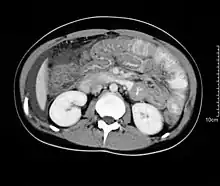

Hypereosinophilia, the hallmark of allergic response, may be absent in up to 20% of patients, but hypoalbuminaemia and other abnormalities suggestive of malabsorption may be present. CT scans may show nodular and irregular thickening of the folds in the distal stomach and proximal small bowel, but these findings can also be present in other conditions like Crohn's disease and lymphoma.